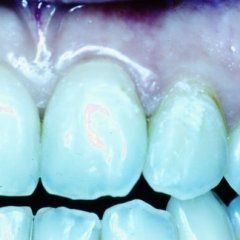

L’enorme diffusione ancora oggi riscontrabile della carie dentaria, unita a traumi, difetti di mineralizzazione o ipoplasie dello smalto determinano la necessità di dover ricorrere ad un restauro dei tessuti dentari lesionati. Il continuo miglioramento dei materiali e di conseguenza delle tecniche hanno altresì ampliato il raggio di azione della cosiddetta conservativa che con il ricorso al trattamento endodontico in caso di lesioni particolarmente gravi, occupa circa i due terzi dell’attività del dentista. In considerazione di questo fatto quindi, oltre all’evidenza che il trattamento restaurativo diretto è in genere il primo atto odontoiatrico che si effettua su una corona dentale lesionata, emerge la necessità che questa terapia sia ben eseguita ed in armonico rapporto con le strutture parodontali ed endodontiche.